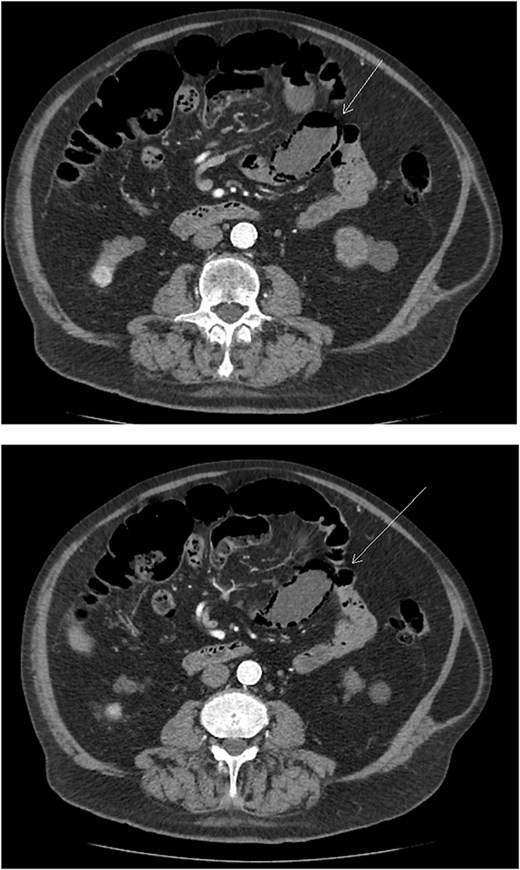

A follow-up CT three months later showed a slight increase in the kidney lesion size but no evidence of surface or distant metastasis. Notably, PI of the small bowel was observed (Fig. 1) but there were no findings of bowel ischemia (BI) or obstruction, such as mesenteric ischemia (MI), bowel wall thickening, ascites, or pneumoperitoneum.

Axial abdominal CT scan image where the arrow points to the presence of pneumatosis intestinalis.